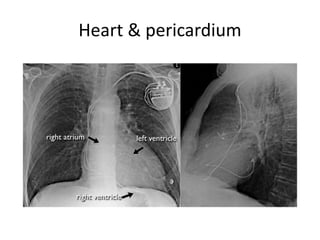

Heart & pericardium

CXR systematic approach

• Whenever you review a chest x-ray, always use a systematic

approach.

We use an inside-out approach from central to peripheral.

First the heart figure is evaluated, followed by

mediastinum and hili.

Subsequently the lungs, lungborders and finally the chest

wall and abdomen are examined.

• You have to know the normal anatomy and variants.

Find subtle abnormalities by using the sihouette sign and

mediastinal lines.

Once you see an abnormality use a pattern approach to

come up with the most likely diagnosis and differential

diagnosis.